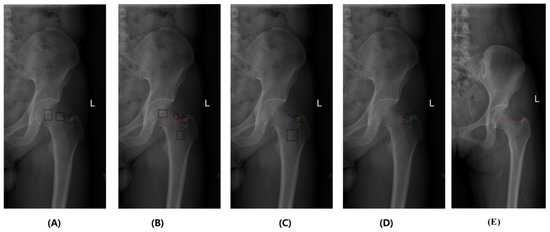

4.1.3. 2D Hip Radiograph Dataset